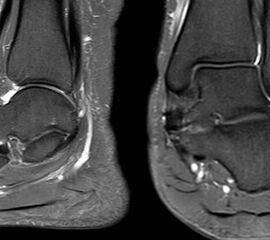

Die Abbildungen 4.2.a bis d zeigen den typischen Aspekt einer talacalcanearen Coalitio. Es besteht nur eine linksseitige, symptomatische Coalitio talocalcaneare (4.2.a und c); das 35 Tage zuvor angefertigte MRT zeigt keine auffälligen Signalveränderungen (4.2.b und d).

Abbildung 4.3. zeigt die Ursache für rechtsseitige Sprunggelenksbeschwerden bei einem Patienten mit talocalcanearen Coalitionen: nur die osteochondrale Läsion an der distalen rechten Tibia ist die Ursache des Schmerzes. Die bilateralen talocalcanearen Coalitionen sind asymptomatisch.